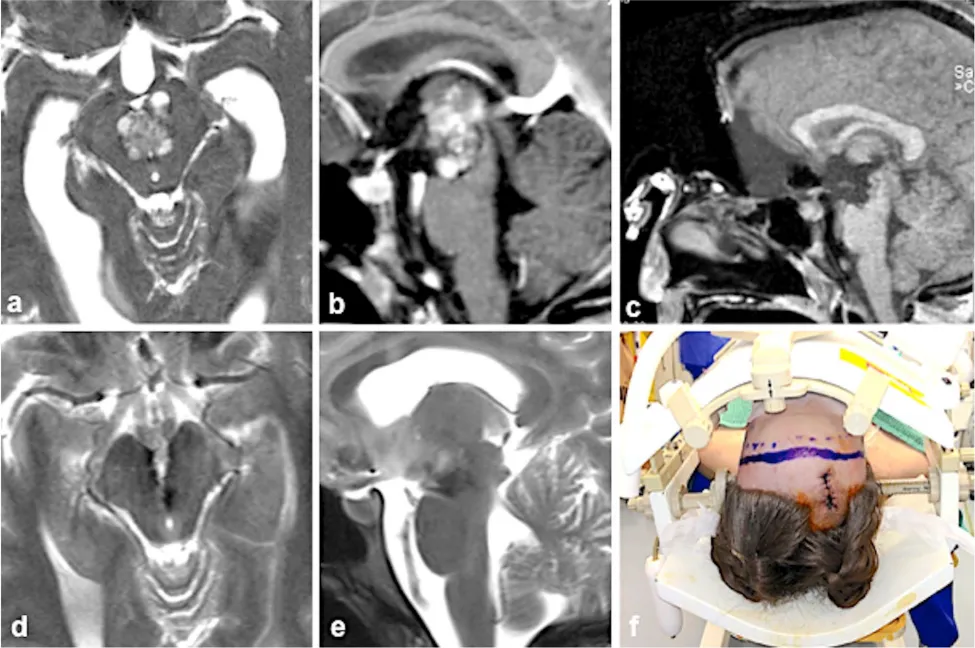

提到脑干手术,很多人会想到手术禁区这个词。尤其是中脑海绵状血管瘤,这类位于脑干核心区域的病变,过去常被认为越深越危险,甚至被排除在手术选项外。 INC国际脑干手术大咖Helmut Ber...